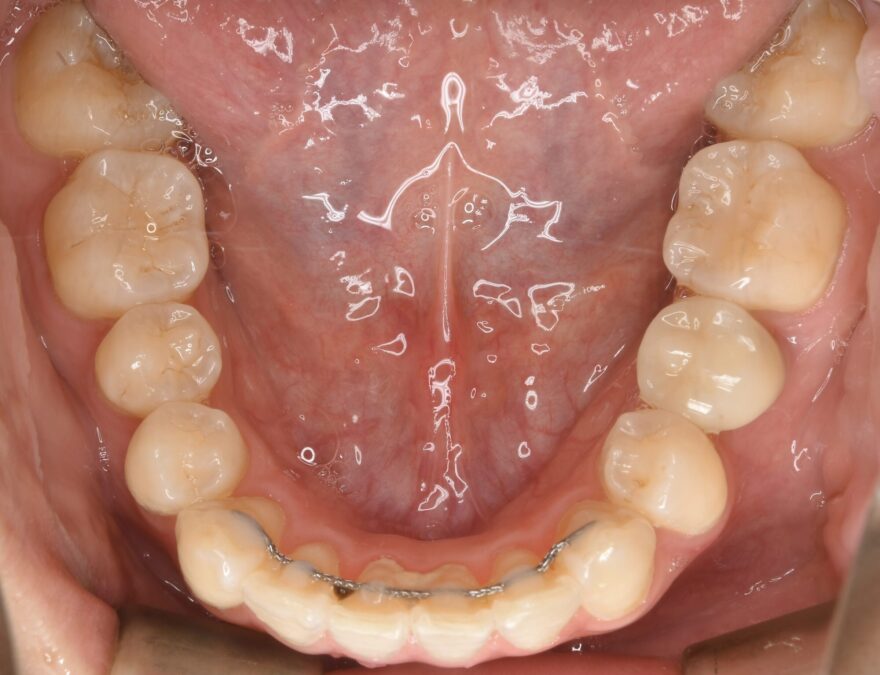

治療後の口腔内写真

約2年の治療期間で、ここまで美しい歯並びになりました。

前歯も綺麗に並びました。

インプラントの上部構造は仮歯からセラミック歯へと交換しています。

下顎の前歯にはワイヤーによる保定装置を装着しました。